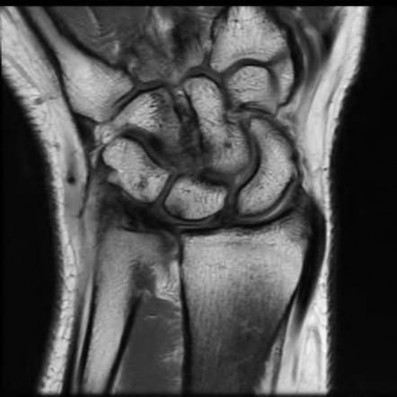

A 22-year-old male falls onto an outstretched hand and sustains a displaced fracture through the proximal pole of the scaphoid. Avascular necrosis of the proximal pole is highly likely due to the disruption of its primary vascular supply. Which vessel provides this critical retrograde perfusion?

Explanation

The primary blood supply to the scaphoid is from the dorsal carpal branch of the radial artery, which enters the dorsal ridge of the scaphoid at the waist and courses proximally. This retrograde blood flow makes proximal pole fractures highly susceptible to avascular necrosis and nonunion. The superficial palmar branch provides a minor supply (about 20%) to the distal pole.